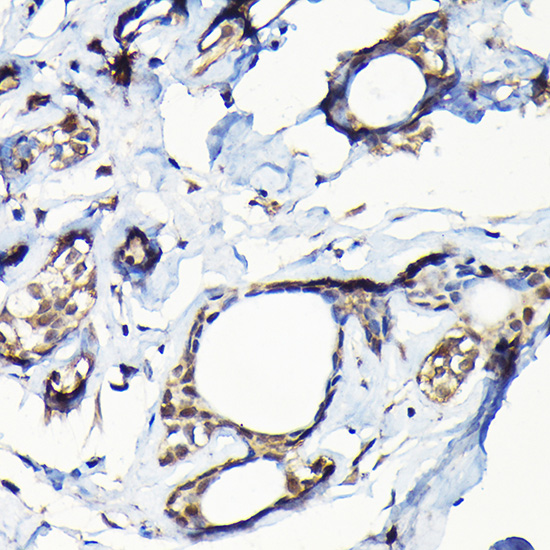

Immunohistochemistry of paraffin-embedded human lung cancer using USP5 Rabbit pAb.

Immunohistochemistry of paraffin-embedded human breast cancer using USP5 Rabbit pAb.